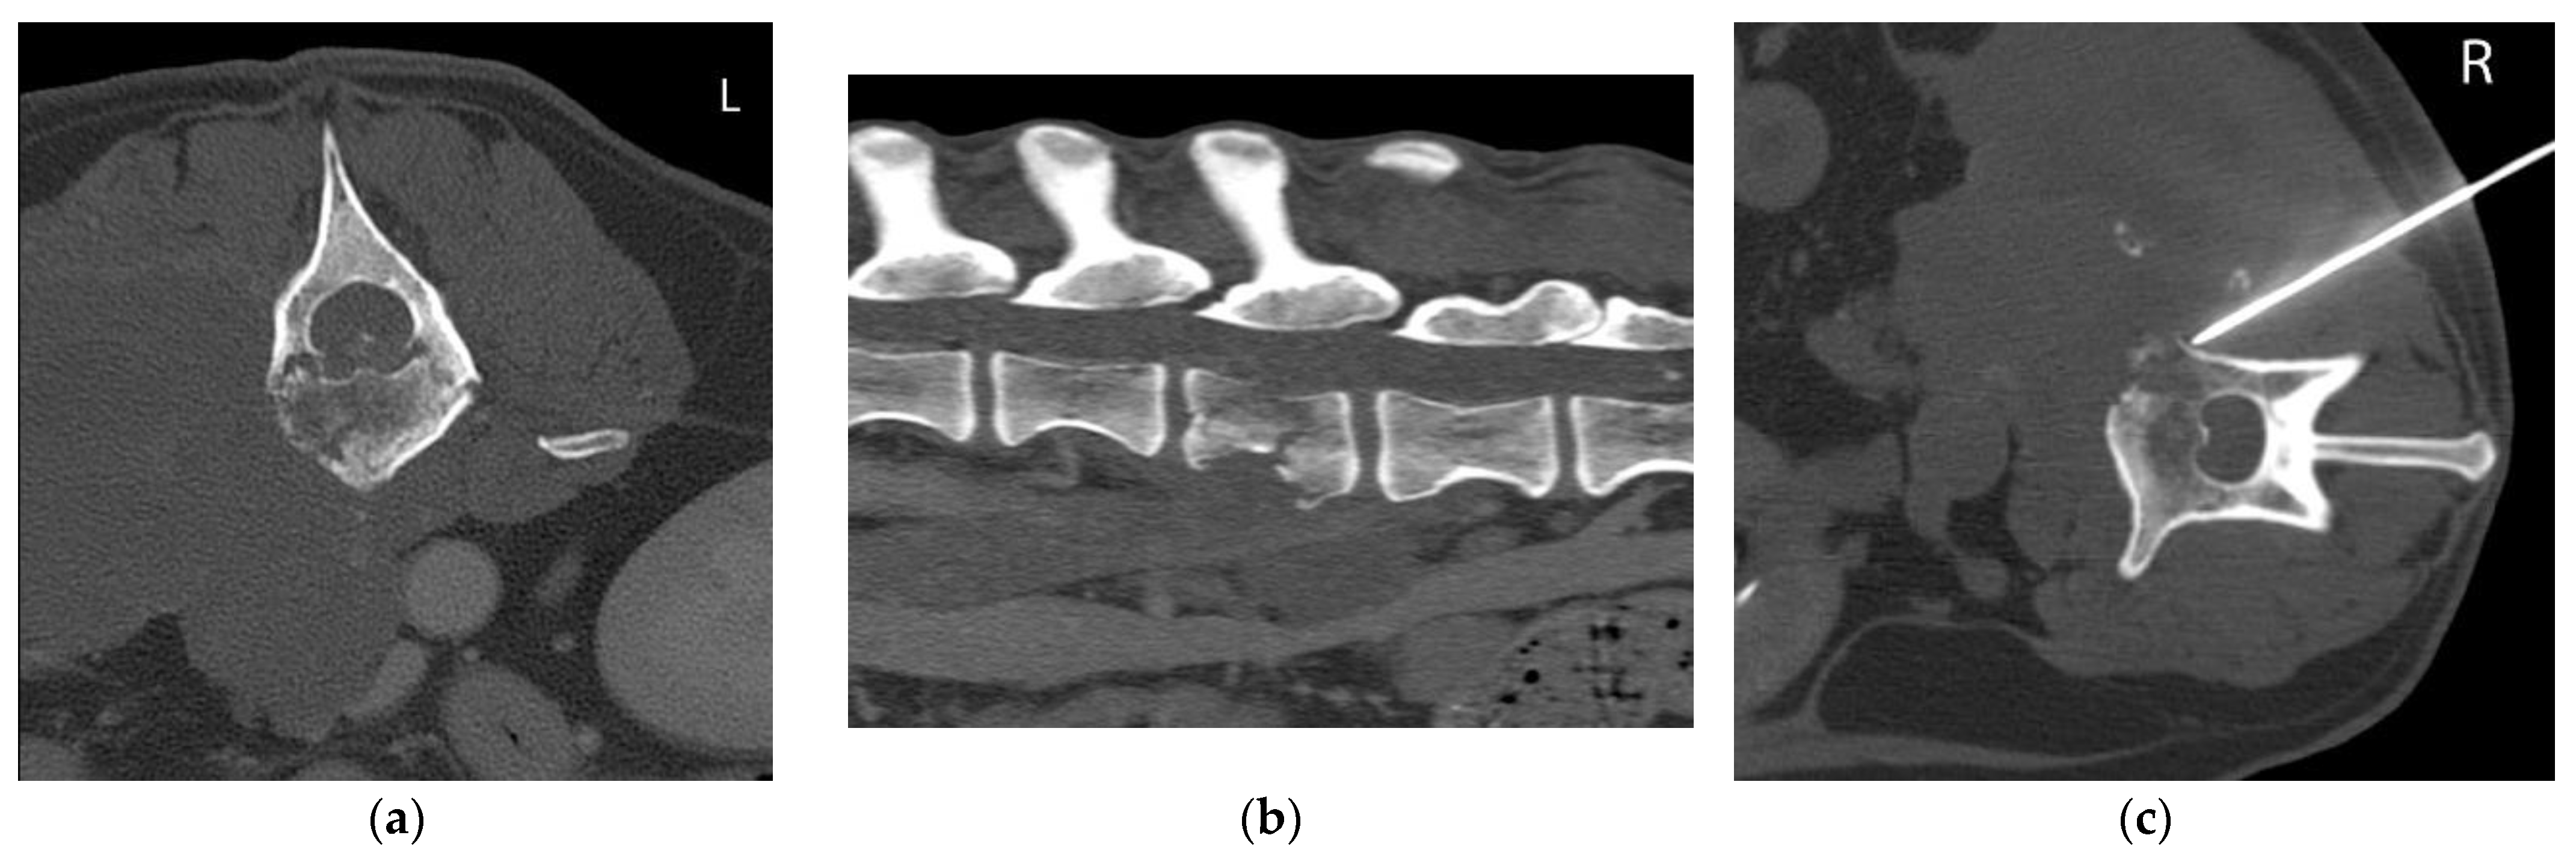

2.2. Equipment and Technique

| 6 | Canine Weimaraner Female intact 13 yo | Chronic progressive weakness and incoordination of the HLs and spinal pain | NE: Ambulatory paraparesis. Absence of PR and normal SR in the HLs. TL hyperesthesia. NLoc: T3-L3 myelopathy | Large mass in right hypaxial muscles infiltrating VB and TP of L3 and L4 and retroperitoneal space (CVC). Pathological fracture of L3 VB with vertebral compression. Lung nodules and periaortic lymphadenopathy. Soft tissue sarcoma | Right L3 VB/ TP and hypaxial mass | Mesenchymal tumor consistent with sarcoma | |

| 11 | Canine Crossbreed Male intact 9 yo | Chronic neck pain. Acute right FL tremors and lameness | NE: Ambulatory tetraparesis. Reduced PR with normal SP in all 4 limbs. Severe hyperesthesia in the C-spine NLoc: C1–C5 myelopathy | Monostotic aggressive bone lesion in C6 (osteolytic and osteoproductive), mainly right-sided, with moderate extradural compression of the spinal cord. Primary bone tumor | Right C6 cranial articular process. | Not diagnostic | Osteosarcoma (surgical biopsy) |